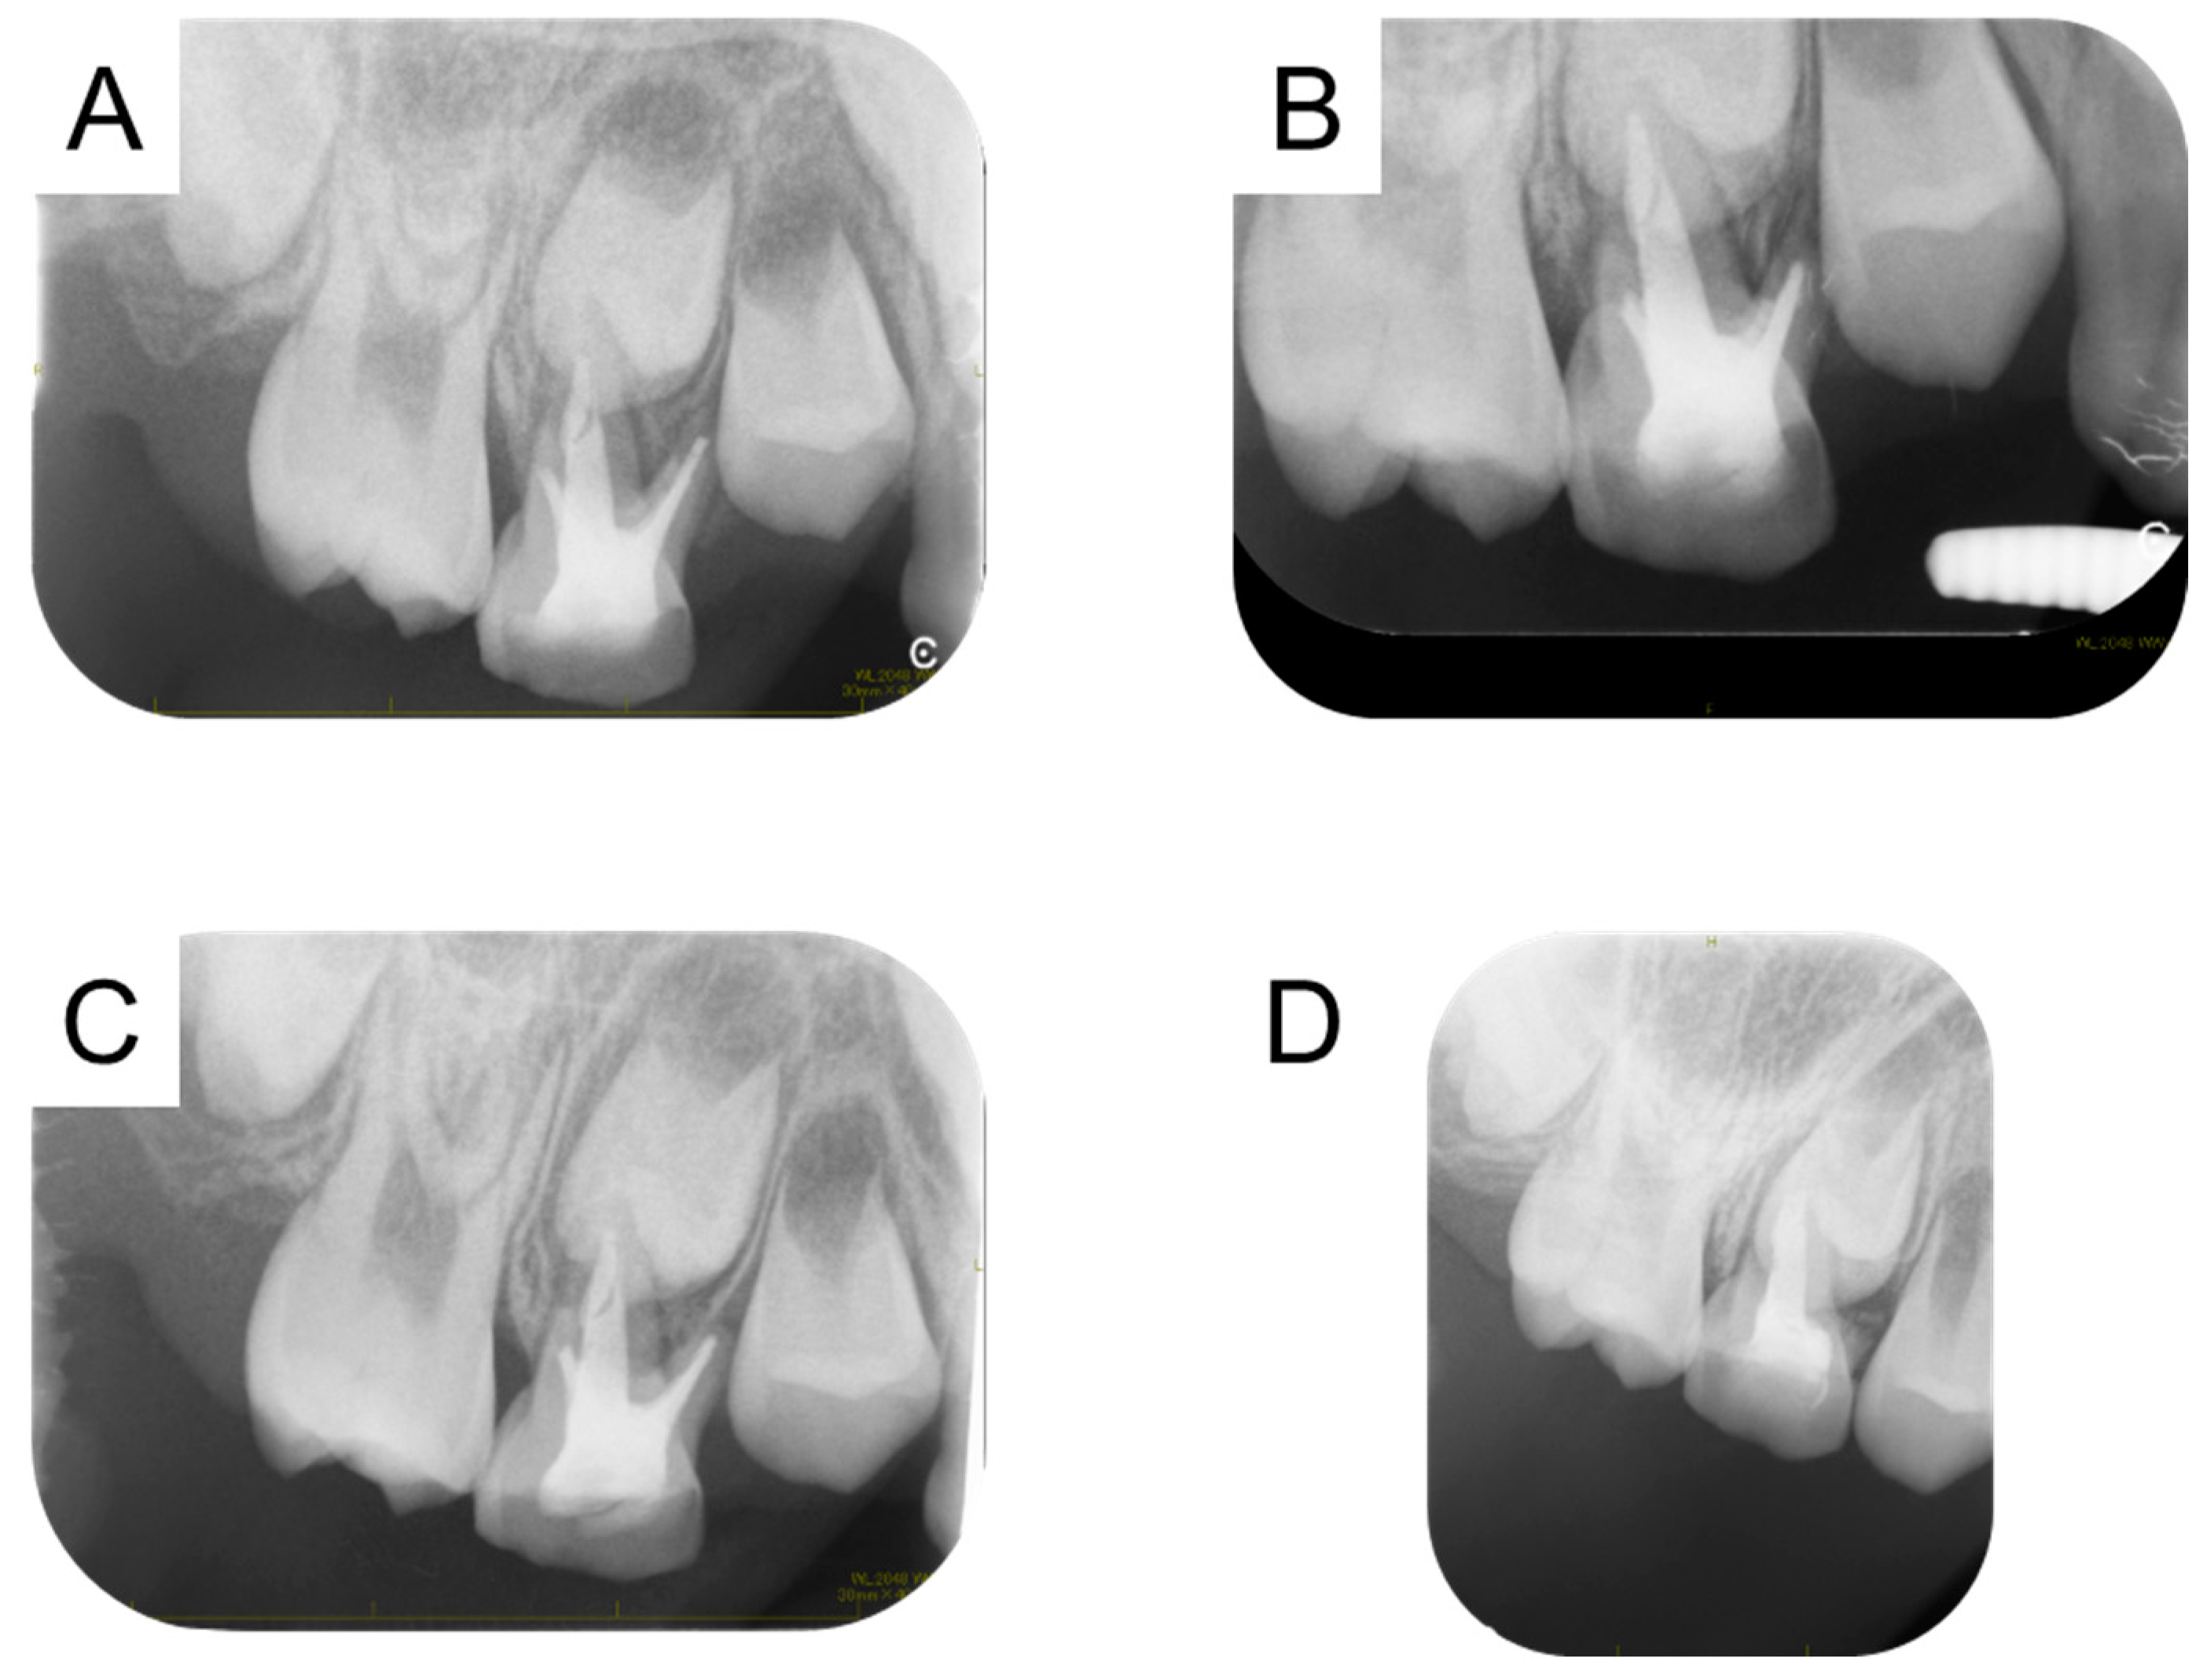

2. Detailed Case Description

| Present case | #55 | Mesio-buccal canal | Reamer | 17 months | Enamel hypoplasia |